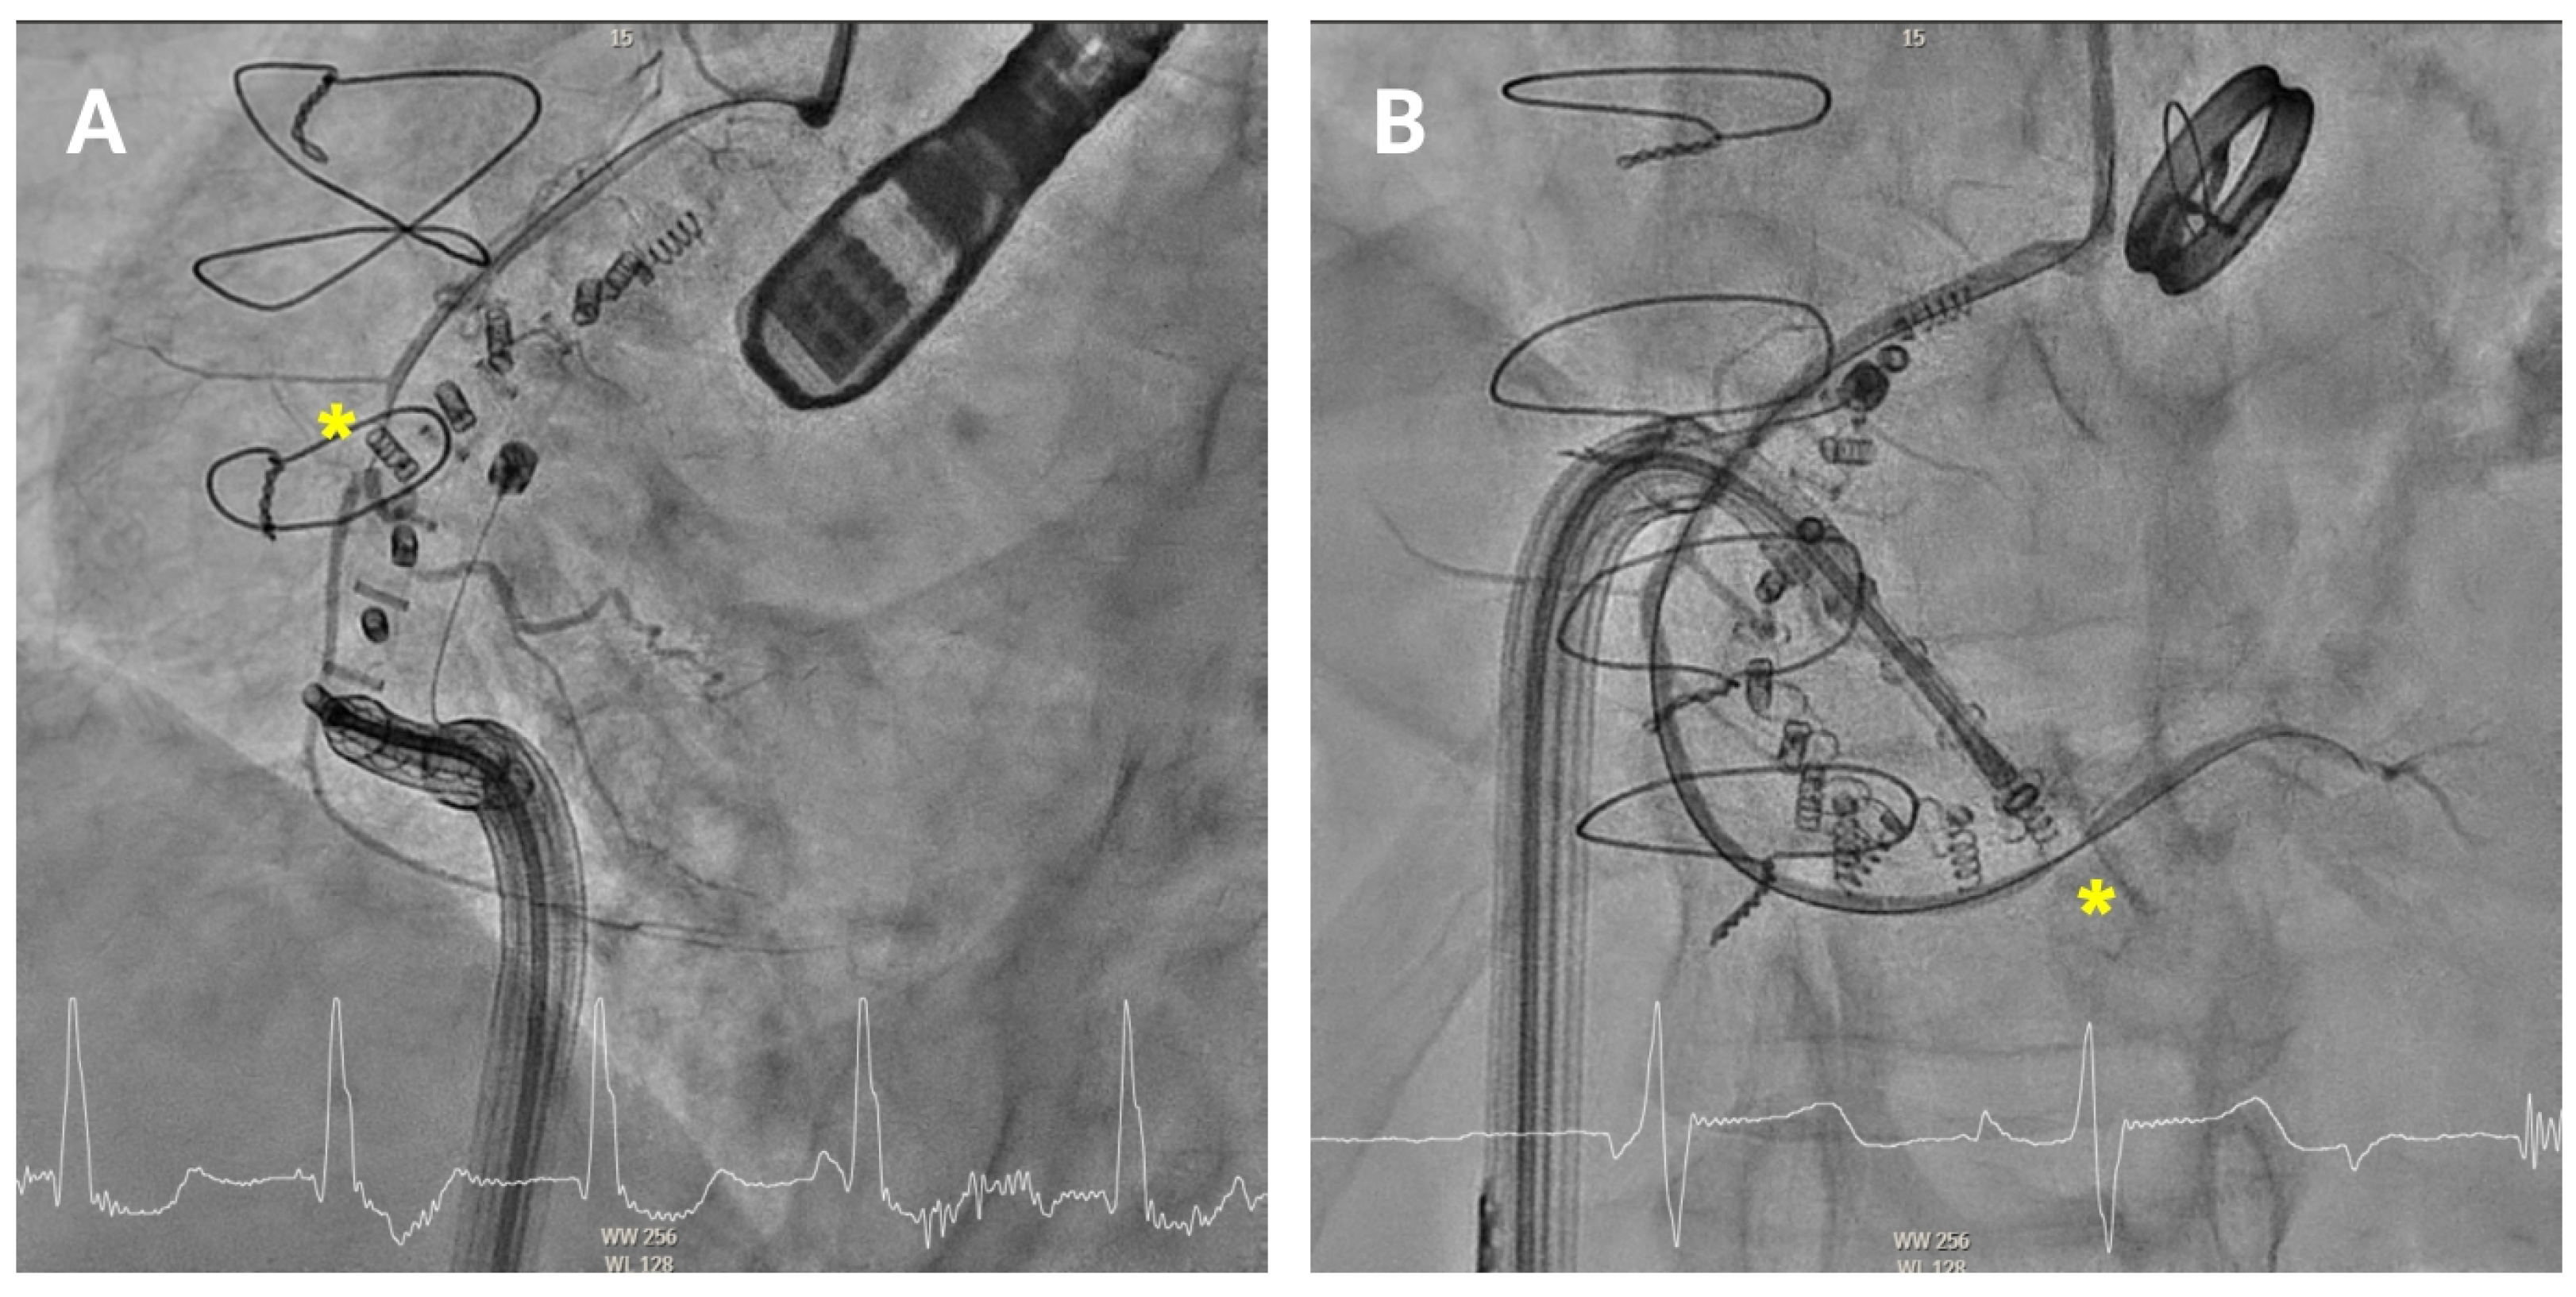

4.3.4. Posterior Annulus (Hooking)

Anchoring along the posterior annulus (

Figure 6A) poses unique challenges due to its parallel alignment with the echo beam and distance from the probe. At this point, the device often needs to be curved in an angle of 90° between the IC and the TSS (“hooking”) to cross the RCA and properly reach the anchor points (

Supplemental Video S2). A mid-esophageal MPR view and a transgastric view at 150° provide a better view of this segment. RAO and LAO projections are employed to verify the alignment of the IC with the annulus and ensure there is no contact with unintended structures [

4.3.5. Posteroseptal Commissure

Finally, as the band approaches the posteroseptal commissure (

Figure 6B), deep esophageal and mid-esophageal bicaval views ranging from 0° to 135° may facilitate visualization of the coronary sinus and the septum, which are critical during this phase [

Figure 6.

Posterior tricuspid annulus anchoring. (A) Posterior annulus anchoring requires navigating anatomical complexity due to echo beam alignment and distance from the probe. A 90° “hooking” angle between the implant catheter and the transvenous steerable sheath is often necessary to overcome the right coronary artery and access the posterior annular region. Transgastric transesophageal view (150°) and upper esophageal retroflexed views aid visualization, while RAO and LAO fluoroscopic projections confirm alignment and proper catheter trajectory. (B) Final anchoring at the posteroseptal commissure using deep and mid-esophageal bicaval views (0–135°) for visualization of the coronary sinus and septum. RAO projection and biplane imaging help verifying proper anchor placement and avoiding overlap or misalignment with nearby structures.